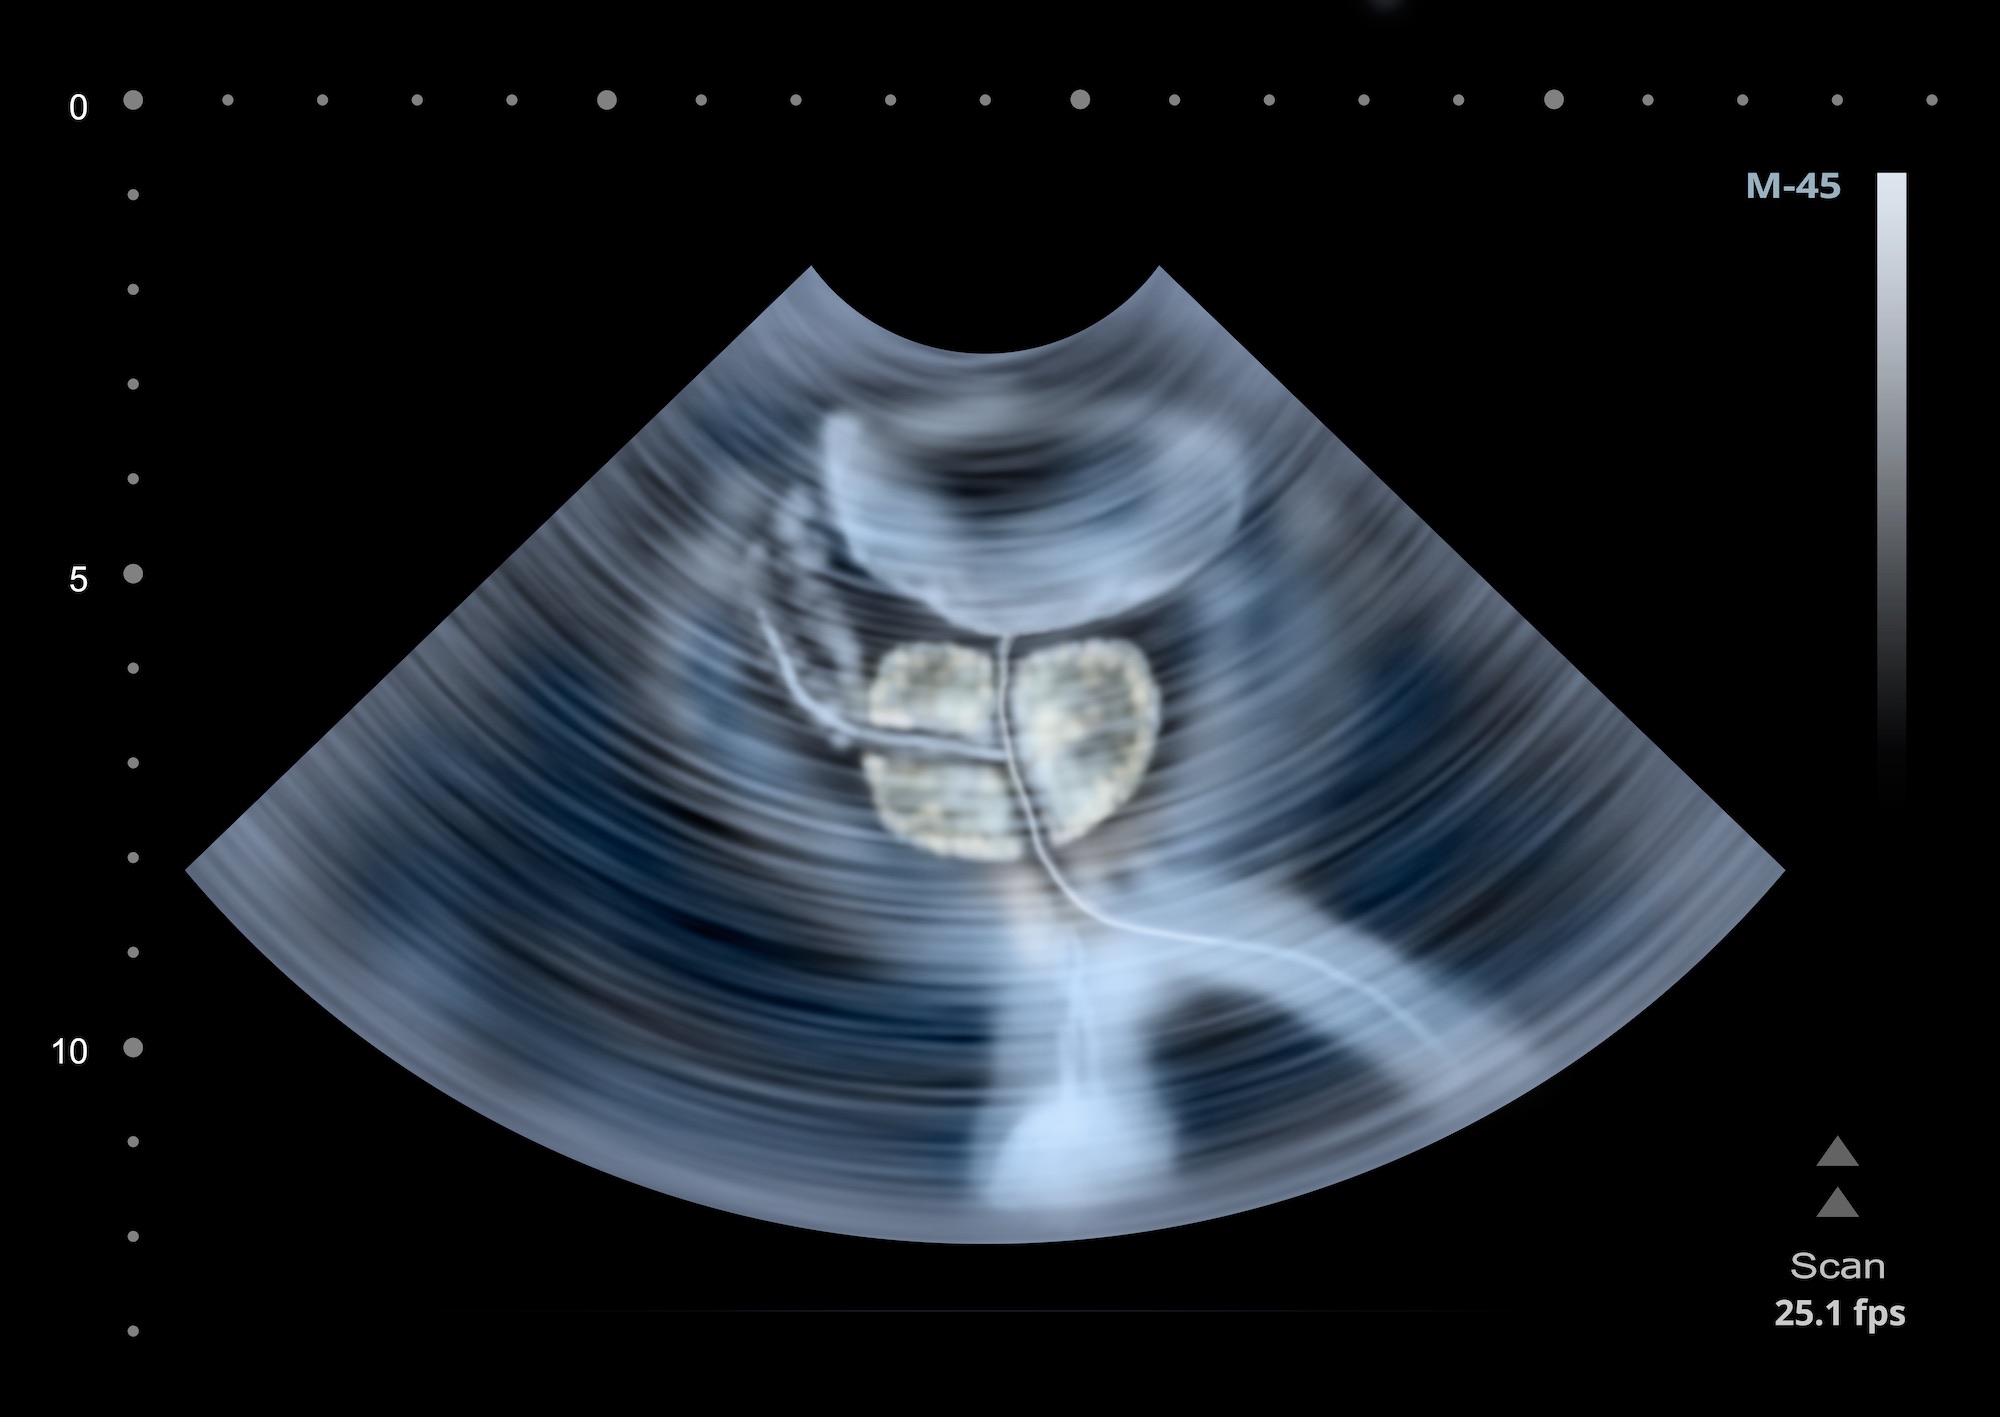

Selon une nouvelle étude, les ultrasons focalisés guidés par IRM (MRgFUS) restent prometteurs chez les hommes atteints d'un cancer de la prostate à risque intermédiaire, avec un contrôle efficace de la maladie et moins d'effets secondaires que les autres traitements.